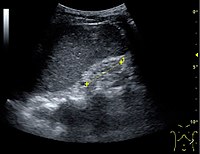

Ultrasound[edit | edit source]

Kidney ultrasonography is useful for diagnostic and prognostic purposes in chronic kidney disease. Whether the underlying pathologic change is glomerular sclerosis, tubular atrophy, interstitial fibrosis or inflammation, the result is often increased echogenicity of the cortex. The echogenicity of the kidney should be related to the echogenicity of either the liver or the spleen (Figure 22 and Figure 23). Moreover, decreased kidney size and cortical thinning are also often seen and especially when disease progresses (Figure 24 and Figure 25). However, kidney size correlates to height, and short persons tend to have small kidneys; thus, kidney size as the only parameter is not reliable.[44]